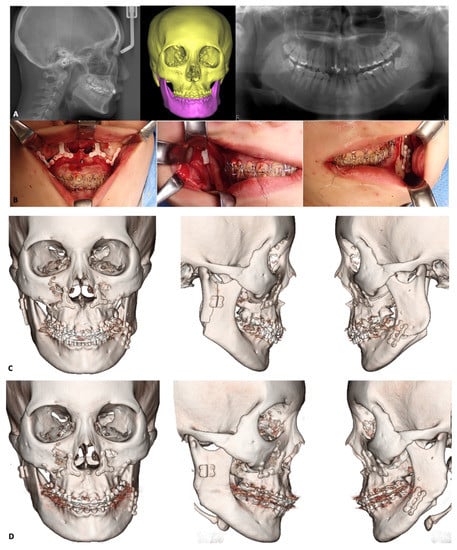

3.2. Orthognathic Surgery

3.2.1. Le Fort I osteotomy

3.2.2. Mandibular Osteotomies